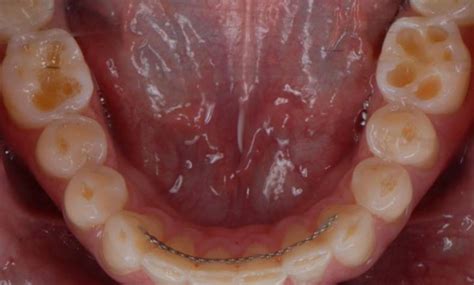

El limón al ser un alimento ácido afecta directamente a la boca. "No existe ningún problema dentario que se solucione con agua con limón en ayunas, sino todo lo contrario. Los odontólogos nos encontramos en muchas ocasiones con pacientes con problemas orales ocasionados por la presencia de ácido de forma prolongada en la boca. Estos problemas pueden ser en los tejidos blandos de la mucosa oral, produciéndose úlceras y erosiones, o en los tejidos duros, asociándose a desgastes dentarios y otras erosiones", explica Carmen Martín Carreras-Presas, profesora de Patología Médica Bucofacial y directora del Máster en Estética Dental en la Universidad Europea.

El ácido del limón afecta al esmalte dental favoreciendo su desmineralización, el esmalte se vuelve más poroso y si este proceso continúa se puede llegar a perder una cantidad importante de esmalte, esto dejaría al descubierto la dentina, que es la parte interna del diente que es mucho más blanda y menos resistente al ataque ácido de las bacterias que producen la caries.

La situación puede empeorar en determinadas circunstancias: "si combinamos, además, la presencia de ese ácido con un hábito de apretamiento dentario como el bruxismo obtenemos como consecuencia el desgaste dentario, la presencia de erosiones en los dientes que se asocian a hipersensibilidad dentaria, y en casos severos a una pérdida funcional, lo que requiere la restauración de la superficie de diente perdida".

El pH fisiológico de la cavidad oral debe ser cercano a 7. Si consumimos bebidas ácidas, como zumos de limón, pomelo, o bebidas carbonatadas, el pH baja, volviéndose ácido. Los tejidos dentales son muy sensibles a esos cambios de pH, comenzando a reblandecerse el esmalte cuando el pH alcanza cifras cercanas a 5 provocando erosión o desgaste de las estructuras dentales, empezando por el esmalte y en los casos más avanzados en la dentina.

Esta erosión del esmalte y la dentina afecta directamente a la estabilidad de tus dientes, haciéndolos más frágiles. La ingesta diaria de limón puede lesionar nuestro esmalte dental. Puede producir un desgaste irreversible del esmalte produciendo la pérdida del mismo, dando lugar a problemas severos como la caries, la sensibilidad y la pérdida estructural de los dientes.